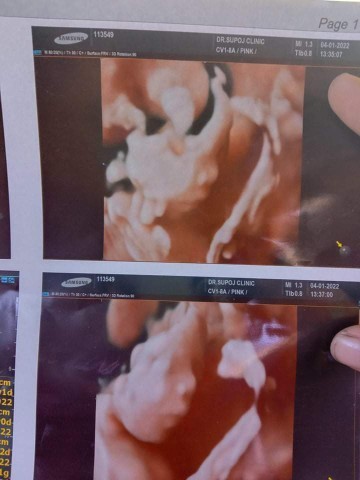

ท้องที่2 จ้า ผู้ชาย 19 สัปดาห์แย้วววว

เอามือก่ายหน้าผากเครียดนิดนึง 22W2d💓